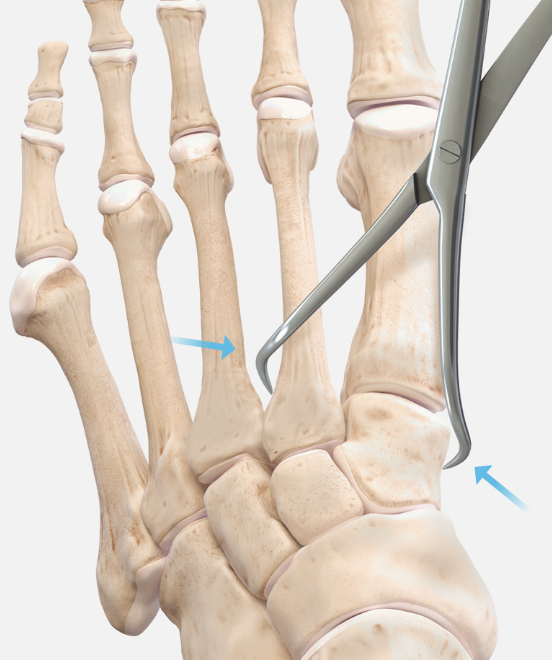

Approach and reduction

Dorsal incision between 1st and 2nd metatarsal

- protect branches of superficial peroneal nerve

- release EHL tendon and retract laterally for 1st TMT / medially for 2nd TMT

- retract EDB more proximally either way to approach 1st TMT / 2nd TMT

- pass artery clip under dorsalis pedis / deep peroneal nerve and mobilize

Reduction

- medial incision over medial cuneiform

- clamp medial cuneiform to base 2nd metatarsal